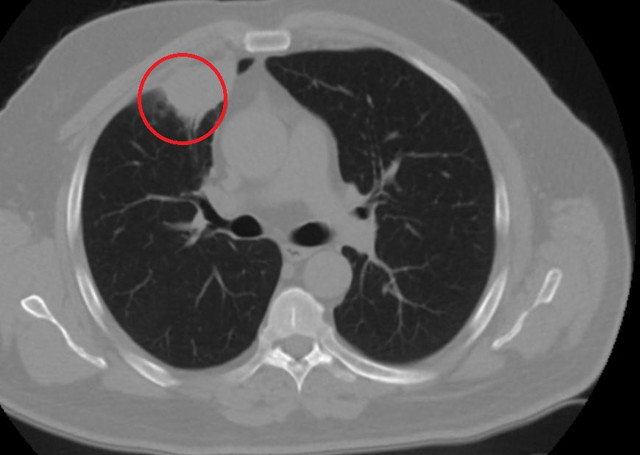

Abone olKent dışında çalışan N.T.'nin, göğüs ağrısı şikayetiyle gittiği hastanede çekilen tomografisinde sağ akciğerinde 4 santimetre çapında tümör tespit edildi. Kanser olabileceği şüphesiyle yapılan ileri tetkikler sonrası N. T.'ye akciğer kanseri teşhisi kondu ve acil ameliyat kararı verildi. Bunun üzerine N.T., ameliyat için memleketi Kahramanmaraş'a geldi. Sütçü İmam Üniversitesi Sağlık Uygulama ve Araştırma Hastanesi Göğüs Cerrahi Anabilim Dalı Öğretim Üyesi Dr. Fatoş Kozanlı da tomografi ve test sonuçlarına göre N. T.'ye akciğer kanseri teşhisi koydu ve ameliyat yapılması gerektiğini söyledi.

"Hastamız, çalıştığı başka bir kentte göğsünden darbe alıyor ve ağrıları geçmeyince bir üniversite hastanesine başvuruyor. Burada hastaya bir akciğer grafisi çekiliyor. Sağ akciğerinde bir kitleye rastlanıyor. Daha sonra hastaya, bir akciğer tomografisi çekiliyor ve göğüs cerrahisi için önemli büyüklükte olan 4 santimetre çapında, akciğer kanserine benzer özellikte radyolojik bulgular olan bir kitle tespit ediliyor. Daha sonra hastaya yapılan ileri tetkiklerde akciğer kanseri teşhisi konuluyor. Hastaya bir cerrahi planlanıyor. Hasta Kahramanmaraşlı olduğu için kendi memleketine gelmeyi tercih ediyor. Bize başvurdu ve göğüs ağrısı şikayeti vardı. Öksürük, nefes darlığı, balgam çıkarma, ateş gibi şikayetleri yoktu. Hastayı biz de değerlendirdik ve ameliyat olmasına karar verdik. Çünkü akciğer kanserine çok benzer radyolojik bulguları vardı. Sağlık Bakanlığımızın kuralları gereği her hastayı ameliyat öncesi PCR testi yapılır. Biz de ameliyat gecesi hastadan PCR testi aldık ve testi pozitif geldi. Ameliyatımızı 14 gün erteledik ve hastamıza koronavirüs tedavisi uygulandı. Hasta 14'üncü gün tekrar bize başvurdu ve yapılan PCR testi negatif çıktı. Yeni bir tomografi çektik ve tümörün tamamen ortadan kalktığını gördük. Şimdi sonuç bilgilerinden başlangıca gittiğimizde, bu bir akciğer kanseri olsaydı, ortadan kalkması mümkün değildi. Başka bir patolojiye bağlı durum olsaydı, yine verdiğimiz tedaviyle ortadan kalkmasını çok beklemeyiz. Antiviral tedavisi verdik ve hastanın radyolojik bulguları neredeyse tamamen normale döndü. Hastaya bunu izah ettik, 'Dünya literatüründe hiç görülmeyen bir radyolojik bulgu' diyerek. Bu gördüğümüz manzara artık hastanın akciğer grafisinde yok, akciğer kanseri değil. "